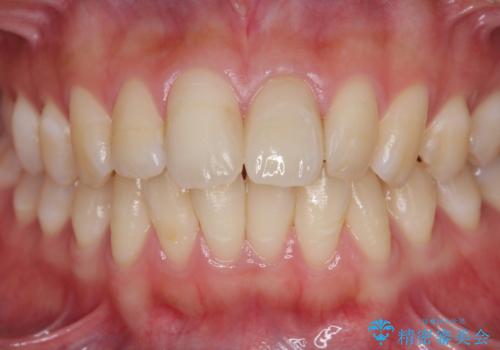

歯科技工士との綿密な打ち合わせで、非常に自然なセラミッククラウンを作製することができました。